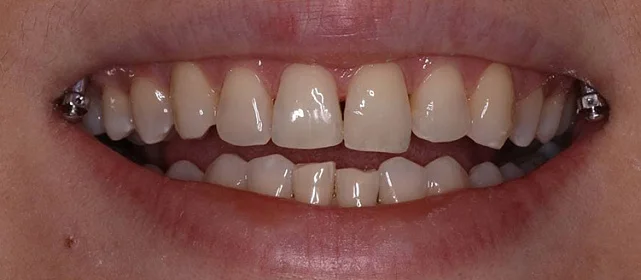

Проблема: Пациентка обратилась с одной жалобой — неровные зубы. При осмотре обнаружили, что обе челюсти сужены, зубам банально не хватает места, отсюда скученность. Зубы здоровые, ортопедия не нужна — чисто ортодонтический случай.

Решение: Установили брекеты на обе челюсти. Расширили дуги, убрали скученность — всё за 15 месяцев. Визиты раз в 4–6 недель для замены дуг. После снятия зафиксировали ретейнеры на обе челюсти, сняли сканы для кап. Ортопед подтвердил, что протезирование не требуется. Терапевт рекомендовал лечение — пациентка записана.

Зубы выровнены, скученность устранена. Установлены несъёмные ретейнеры на обе челюсти, сняты сканы для ретенционных кап. Ортопедия не требуется, рекомендовано лечение у терапевта.

Пятнадцать месяцев!! Я морально готовилась к двум годам минимум, начиталась всякого в интернете. Виктория Юрьевна на первой консультации сказала, что случай не самый сложный и должны уложиться побыстрее. Так и вышло. Из неприятного — первая неделя после установки и пара дней после каждой замены дуги. В остальном нормально, привыкла быстро. Когда сняли и я увидела зубы — не поверила, что это мои. Теперь вот к терапевту надо сходить, подлечить пару зубов, и вообще всё.